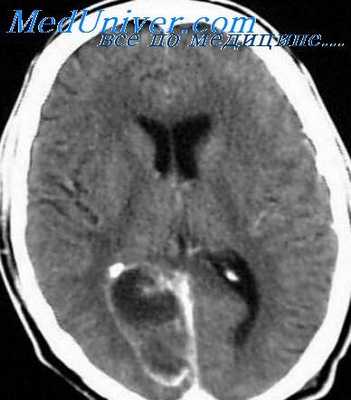

Решающим для подтверждения диагноза менингита является исследование цереброспинальной жидкости. По показаниям проводят дополнительные исследования (рентгенографию черепа и придаточных пазух носа, осмотр глазного дна, электроэнцелографию, эхо-энцефалографию, компьютерную и ядерно-магнитнорезонансную томографию). При люмбальной пункции определяют давление цереброспинальной жидкости, проводят ликвородинамические пробы Стуккея и Квикенштедта, определяют визуальные характеристики жидкости (прозрачность, цвет). В осадке жидкости определяют количество и состав клеток, наличие микрофлоры. Проводят биохимические (количество белка, глюкозы, хлоридов, осадочные пробы и т. д.) и микробиологические исследования.

Второе место занимают субарахноидальные кровоизлияния, не связанные с черепно-мозговой травмой. Их причиной является разрыв аневризмы или патологически измененных сосудов оболочек головного мозга. Болезнь начинается с внезапной головной боли (удар в голову), которая сначала может быть локальной, но быстро приобретает диффузный характер. При осмотре выявляется менингеальный синдром, повышение артериального давления. Через два-три дня картина может измениться: головная боль нарастает, наблюдается рвота, температура тела повышается. Это связано с развитием асептического воспаления, не требующего специальной терапии. Такие пациенты должны госпитализироваться в неврологические отделения. Окончательный диагноз устанавливается после исследования цереброспинальной жидкости, которая в этих случаях равномерно окрашена кровью, после центрифугирования — красная, прозрачная (лаковая), позже — мутноватая, ксантохромная. В мазке — эритроциты, нейтрофилы и лимфоциты в различных соотношениях, количество белка повышено, иногда резко, глюкозы — в норме или повышено.